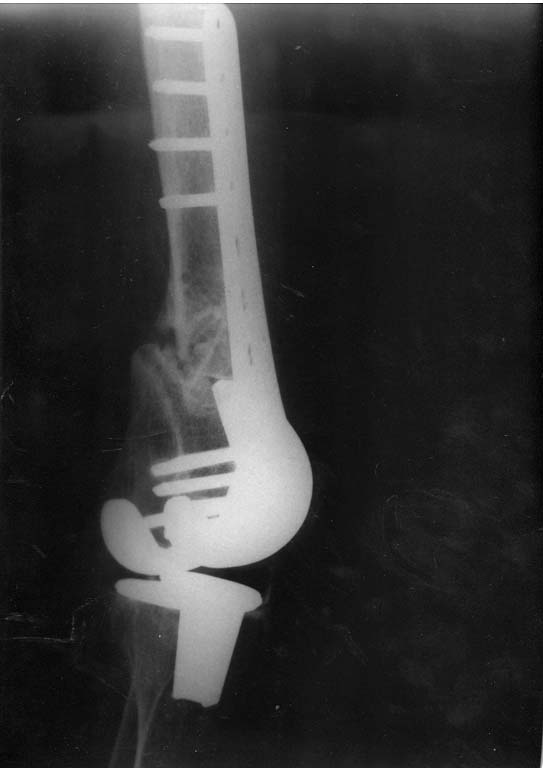

Оперирована по поводу перипротезного перелома н/з бедренной кости Оперирована по поводу перипротезного перелома н/з бедренной кости в ноябре 2010г.Диагноз:закрытый оскольчатый перелом бедренной кости в н/3 со смещением отломков, состояний после эндопротезирования коленного сустава от 2009г.Операция:артропластика коленного сустава, остеосинтез бедренной кости пластиной с угловой стабильностью.В июле операция по поводу несросшегося перелома н/3 бедренной кости,перелом пластины:взятие костного аутотрансплантата из гребня подвздошной кости, удаление пластины, костная аутопластика, остеосинтез бедренной кости пластиной с угловой стабильностью.На контрольном снимке от октября 2012г.- несросшийся перелом бедренной кости, ложный сустав.Что еще можно предпринять? Существуют ли методы лечения, кроме операционных? Поможет ли в данном случае гравитационная терапия7 Или ждать когда все-таки произойдет сращение или еще раз сломается пластина?И произойдет ли сращение вообще? Помогите советом.

Добрый день. Оперировать не рекомендовали. После 3-х лет после операции- вот такая картина. Прокомментируйте пожалуйста снимки.

Снимок только в одной проекции, для более полной оценки ситуации надо и фас увидеть. И в первую очередь узнать о клиническом статусе - жалобы, ось, длина, амплитуда движений в колене, опоросопособность, потребность в дополнительной опоре?

Прошу Вас прокомментировать динамику. Почему пластина опустилась? И наблюдается ли все-таки сращение?